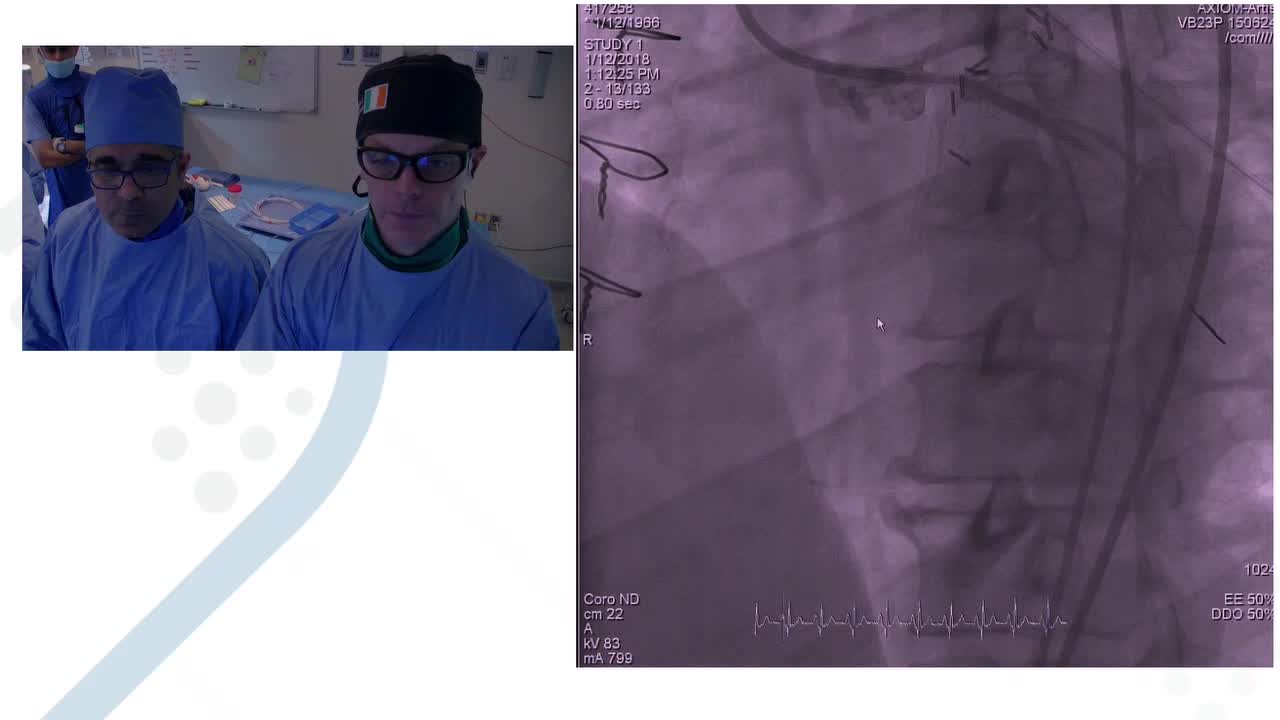

Optima Education

At Optima Education we believe that medical education can be better. Technology is changing and with it the way that we learn. We believe that ideas, concepts and techniques can, and should, be...